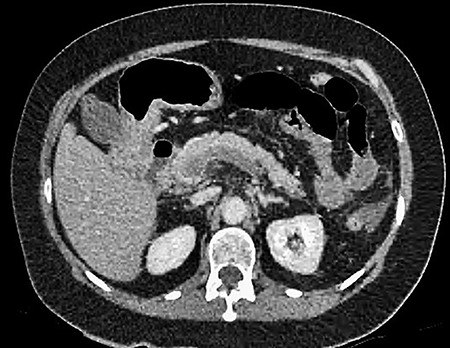

A 61-year-old female presented to a regional hospital with a 3-week history of intermittent diarrhoea, vomiting and generalized abdominal pain. She had a diffusely tender abdomen but was not peritonitic, and was shocked with a heart rate of 110 beats per minute, blood pressure of 89/45 mmHg and was peripherally cool. Her blood tests revealed a lactate of 7.2 mmol/L, which worsened to 7.8 mmol/L during resuscitation with intravenous fluids, and white cell count was 30.9 × 109/L, with an international normalized ratio (INR) of 1.4. She had an acute kidney injury with a creatinine of 119μmol/L and estimated glomerular filtration rate (eGFR) of 43 mL/min/1.73m2. Computed tomography (CT) revealed extensive thickened loops of non-enhancing small bowel with pneumatosis, moderate free fluid and a large splenic infarction. There was extensive thrombosis of the splenic vein and superior mesenteric vein extending into the portal vein to the level of the porta hepatis. Her background history included factor V Leiden and protein S deficiency, for which she had been non-compliant with warfarin during this illness. She had no surgical history (Figs. 1–5).

CT showing an area of splenic infarction due to venous ischaemia.